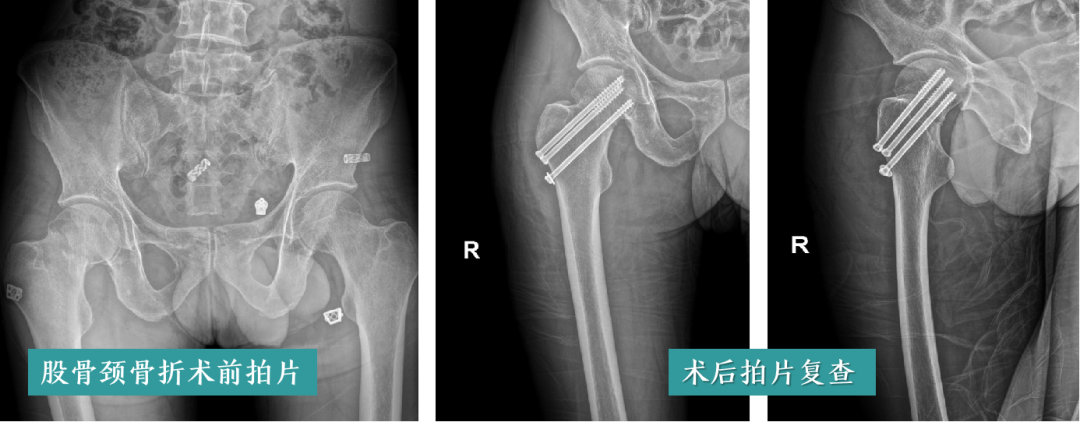

01 高龄老人粉碎性骨折

高龄老人往往伴有多种基础疾病,骨折治疗风险高。科室针对高龄老人的身体状况,制定多学科协作治疗方案,在手术风险评估、麻醉管理、术后护理等方面精益求精,成功为众多高龄老人实施骨折手术,改善生活质量,让高龄不再成为骨折治疗的禁忌。